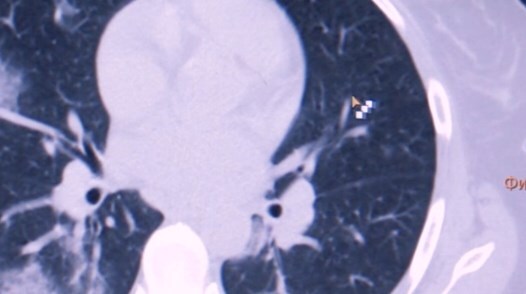

У некоторых пациентов происходят изменения в легких.

Отмечается, что человек чувствует себя нормально, но коронавирус повреждает легочную ткань, на которой образуются уплотнения.

Врач-рентгенолог "Медико-хирургического центра на Пресне" Людмила Леонова пояснила, что воспаленная зона в легких начинает фиброзироваться (фиброз – уплотнение легочной ткани).